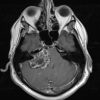

U dây VIII

» Thông tin: Nam giới – 50 tuổi.

» Lâm sàng: Đau đầu + Mất thính giác phải.